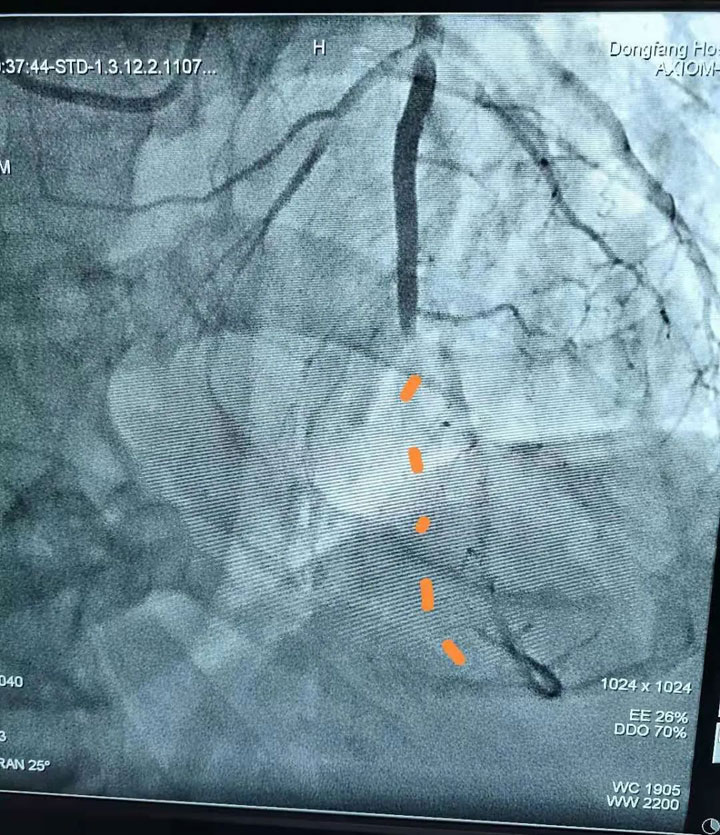

胸痛中心团队医生——心血管内科副主任王其虎、医生宁伟、熊堂鹏为患者施行了急诊冠状动脉造影+取栓术。术中造影发现患者心脏回旋支中端血管完全闭塞,大面积心肌没有血供,医生紧急使用取栓装置由远至近多次抽吸血栓,完成血运重建。“我们采用的这种取栓装置可以直接将大的血栓全部吸出体外,人体内将不再残留小血块,大大降低产生并发症的几率。”心血管内科医生熊堂鹏介绍说,这项技术可以免去冠脉支架的植入,即“介入无植入”,为广大冠心病患者提供了更加安全、有效的治疗手段。